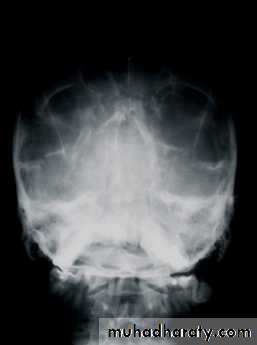

Radiographic Evaluation

• Plain Films• Lateral Skull

• Waters View

• Posteroanterior view of skull

• Submental vertex

• CT Scan

• 1.5 mm cuts

• axial and coronal views

Lateral skull

Water’s ViewCT Scan